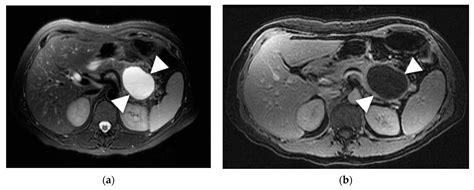

The Role of Magnetic Resonance Imaging (MRI) in the Diagnosis of Pancreatic Cystic Lesions (PCLs)

Understand the causes and symptoms of pancreatic duct dilation. Our expert guide explains why this condition occurs, potential links to pancreatitis or tumors, and the diagnostic tests needed for effective treatment. Learn when to consult a specialist to ensure proper management of your pancreatic health and prevent serious complications.